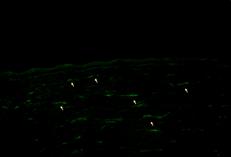

TUNEL阳性细胞在Epi-LASIK与LASEK术后4小时至3天均有较高表达,在术后1天均达到最高峰(见图2、3)。Epi-LASIK与LASEK组术后4小时、24小时、3天和1周的高倍镜下平均TUNEL阳性细胞数与对照组相比,差异有统计学意义(P<0.01);且在该四个时间点Epi-LASIK与LASEK组间相比显示Epi-LASIK有更轻的促凋亡反应,差异亦有显著统计学意义(P<0.01)。

图3 LASEK术后24h角膜TUNEL染色